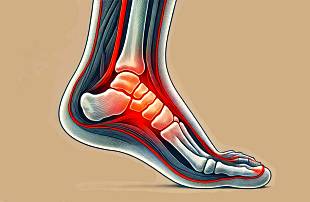

뼈는 단단한 구조물처럼 보이지만 미세한 혈관과 단백질 섬유, 무기질이 교차하며 만들어진 살아 있는 조직이기 때문에 충격을 받을 때마다 고유의 방식으로 반응합니다. 예를 들어 의자 다리에 걸려 중심을 잃고 발목이 급격히 꺾일 때는 비틀림력이 작용하여 나선형 골절이 나타날 수 있습니다.

또한 높은 곳에서 떨어져 발뒤꿈치로 착지할 때는 체중이 압축되며 주상골 같은 작은 뼈가 조용히 눌려 깨지기도 합니다. 이런 부상은 겉으로 보기에는 멀쩡해 보이나 체중을 실을 때마다 날카로운 통증이 번지며 내부의 균열이 자신을 드러내곤 합니다.